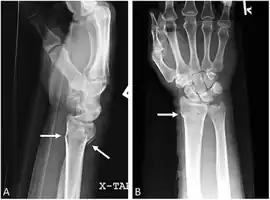

Bilateral Colles fractures/frontal

Bilateral Colles fractures/lateral

The classic Colles fracture has the following characteristics:[7]

- Transverse fracture of the radius

- 2.5 cm (0.98 inches) proximal to the radio-carpal joint

- dorsal displacement and dorsal angulation, together with radial tilt[8]

- Radial shortening

- Loss of ulnar inclination≤

- Radial angulation of the wrist

- Comminution at the fracture site

- Associated fracture of the ulnar styloid process in more than 60% of cases.